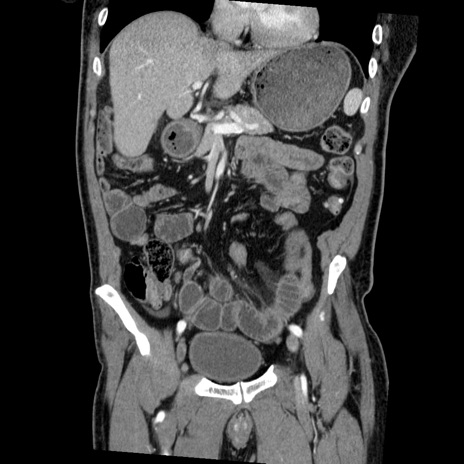

症例22(冠状断像)

【症例】50歳代男性

【主訴】腹痛

【現病歴】AVMからの被殻出血のため回復期リハ病棟入院中。 本日午後3時頃急に下腹部痛が出現した。

【既往歴】AVM、被殻出血、虫垂炎、高血圧

【身体所見】意識晴明、左半身不全麻痺、会話の理解は良好、36.5°C、腹部:膨隆、全体に板状硬、下腹部正中に圧痛点あり、反跳痛-、筋性防御不明、右下腹部にope scar

【データ】WBC 9400、CRP 0.06